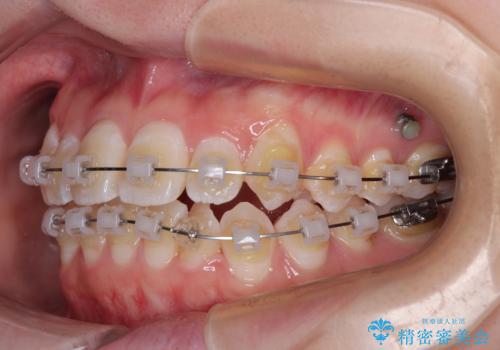

- クリアブラケット

目立ちにくさと費用のバランスを考慮し、プラスチックブラケット+メタルワイヤーを採用。日常生活でも装置の存在感を気にせずお過ごしいただけます。

上下の正中(真ん中のライン)もずれることなく、バランスの取れた美しい歯並びに。笑顔に自信を持てる仕上がりとなりました。